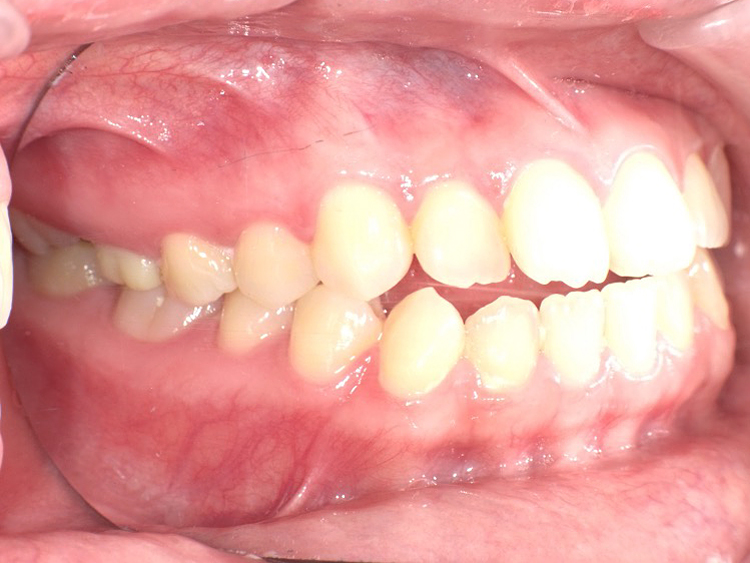

症例3

Before

After

| 主訴 | 上下の歯のガタガタを治したい |

|---|---|

| 年齢 | --- |

| 治療期間 | 約10ヶ月 |

| 治療内容 | インビザラインiGoで上下顎の治療。 狭まっていた歯並びを広げることで、 ガタガタに並んでいた歯を綺麗に並べた。 |

| 治療費 | ¥517,000(税込)+月額調整料 |

| 治療のリスク | 歯と歯の間を削ることでスペースを確保するので、 場合によっては歯が染みる症状が出ることがある。 |